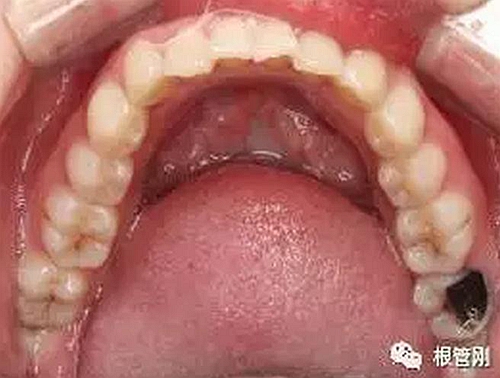

深齲離牙髓炎僅一步之遙,也就意味著離根管治療僅一步之遙。于細(xì)微處見知著,于細(xì)小之處見技術(shù)!不管怎樣,除疾病,還健康,是我們的共同初心,盡醫(yī)生所能,也盡患者所能,方能得始終!

早發(fā)現(xiàn),早治療,永遠(yuǎn)是對(duì)的!